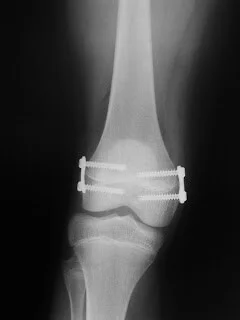

Durante o crescimento, ambas as deformidades podem ser corrigidas pela inserção de grampos ósseos sobre a cartilagem de crescimento. O procedimento é denominado epifisiodese.

Em adultos com menos de 60 anos, existem opções como a osteotomia tibial valgizante para taratar o geno varo ou da femoral varizante para tratar o geno valgo.